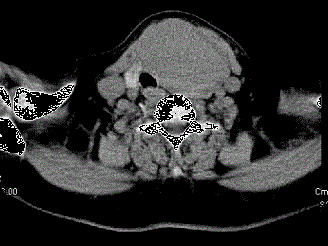

问题 女,56岁,发现颈部肿块一月余,CT如图所示,最可能诊断为 ( )

选项 A、甲状腺腺瘤 B、甲状腺脓肿 C、甲状腺乳头状癌 D、甲状腺原发淋巴瘤 E、甲状舌管囊肿

答案 A